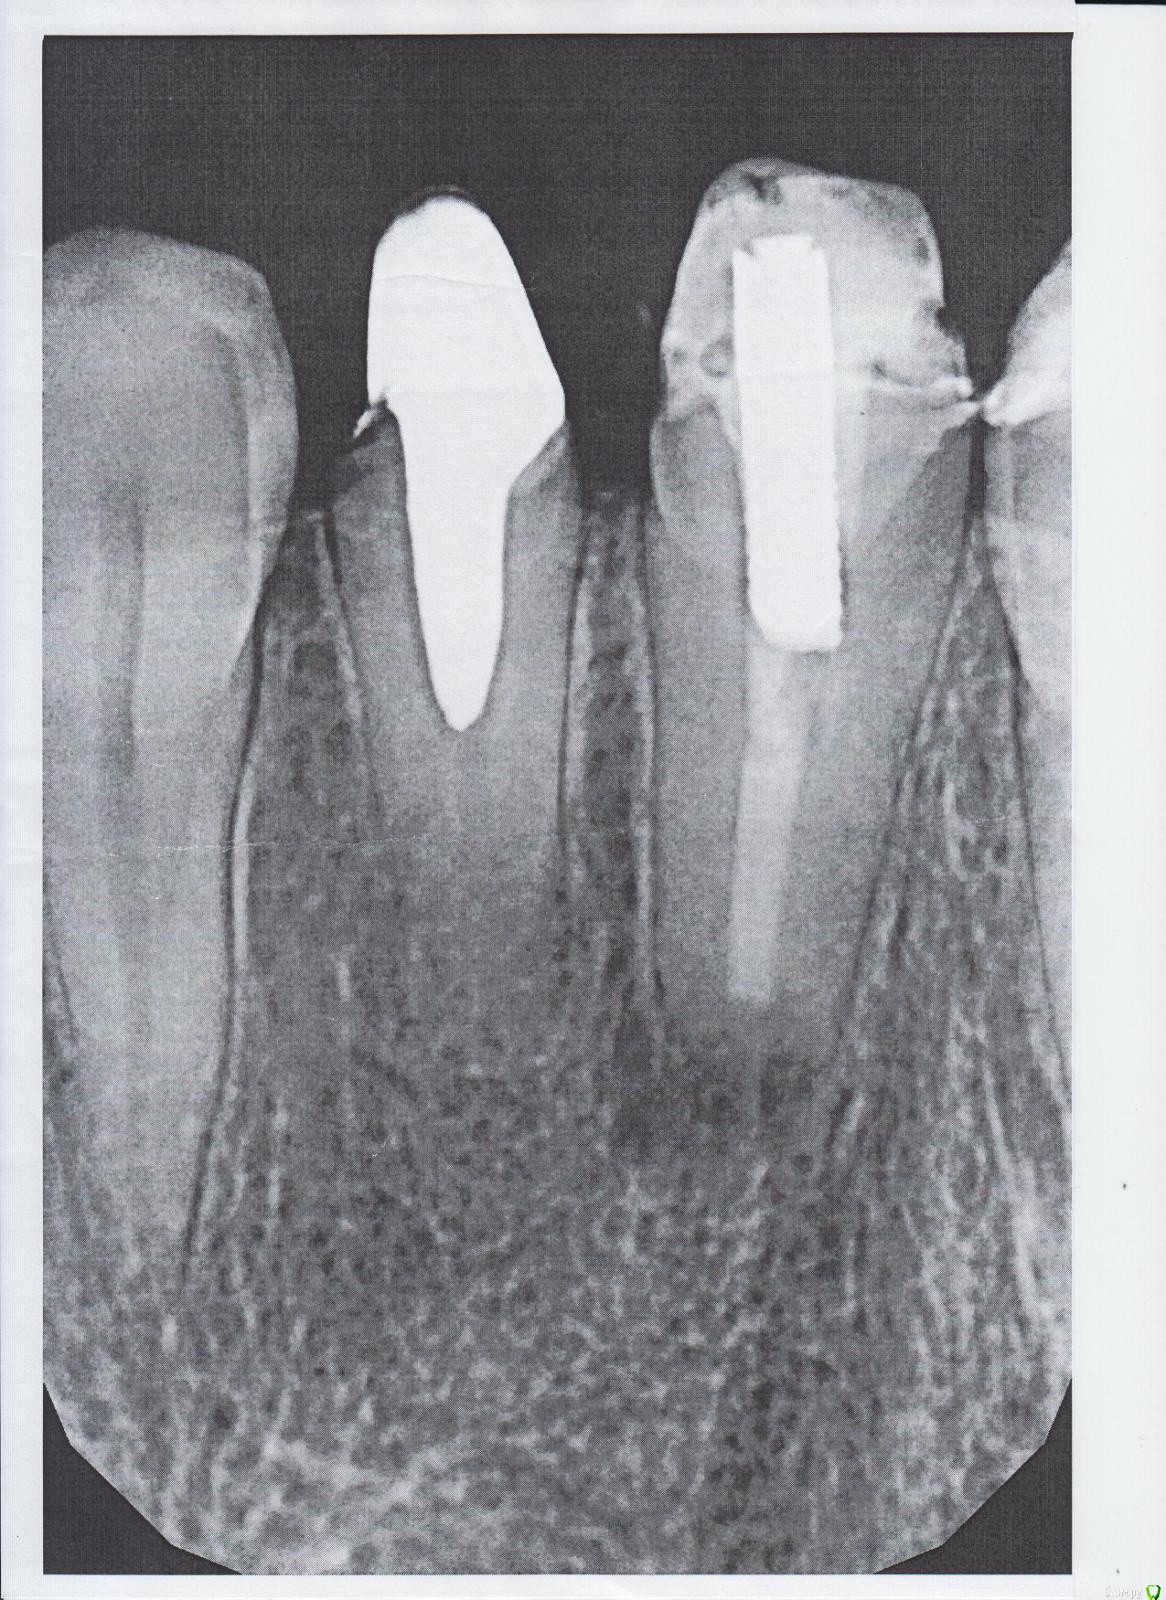

Анастасия33 Опубликовано 29 мая, 2018 Поделиться Опубликовано 29 мая, 2018 Добрый день. Мне нужно было установить коронку на 22 зуб. Обратилась к ортопеду, сделали снимок, снимок показал кисту 22 зуба. Назначена была резекция корня. После ортопед установил мне металлический штифт. Зуб немножко поднывал, я решила обратиться за консультацией в другую клинику. И вот мне сделали снимок и ахнули. Почему канал не пролечили, а штифт вставили.. Это же опять киста будет. Подскажите, пожалуйста, что мне теперь делать, у кого это все перелечивать, как удалять этот штифт, вдруг корень треснет. Ссылка на комментарий

Борис80 Опубликовано 29 мая, 2018 Поделиться Опубликовано 29 мая, 2018 Вы номер зуба точно говорите? штафт в 21 у вас и в 21 канал запломбирован Ссылка на комментарий

Анастасия33 Опубликовано 29 мая, 2018 Автор Поделиться Опубликовано 29 мая, 2018 Да, точно 22 зуб. Может это не штифт правильно называется, а вкладка металлическая. Ссылка на комментарий

red_butler Опубликовано 29 мая, 2018 Поделиться Опубликовано 29 мая, 2018 Вкладку достать, канал перелечить Ссылка на комментарий

Анастасия33 Опубликовано 5 июня, 2018 Автор Поделиться Опубликовано 5 июня, 2018 Добрый день! Подскажите еще, пожалуйста, может ли канал 22 зуба быть запломбирован не рентгеноконтрастным материалом? Ссылка на комментарий

red_butler Опубликовано 5 июня, 2018 Поделиться Опубликовано 5 июня, 2018 Подскажите еще, пожалуйста, может ли канал 22 зуба быть запломбирован не рентгеноконтрастным материалом? если это постоянный материал, то нет Ссылка на комментарий